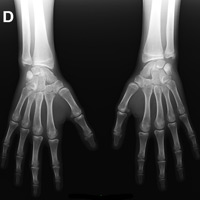

Exames

Raios X

O que é o exame?

O sistema de Raio-X Digital apresenta uma melhor qualidade e precisão da imagem gerada por raio-X principalmente mais saúde ao paciente devido a menor exposição a radiação ionizante.

Os problemas comuns na manipulação e processamento de películas convencionais são minimizados com o sistema de Raio-X Digital, reduzindo desta forma o tempo de realização dos exames e eventuais repetições na aquisição de imagens pois, o sistema digital permite ajustes na imagem captada contribuindo também para uma menor exposição do paciente ao raio-X. O sistema de Raio-X Digital permite ainda o arquivamento de exames possibilitando o estudo comparativo entre exames anteriores e actuais, auxiliando o Médico na definição e no acompanhamento de quadros clínicos.

Como é feito?

O paciente posiciona-se em frente ou sobre o aparelho de raio-x acompanhado da orientação de um técnico. É emitido raio-x na região a ser estudada e ao mesmo tempo os raio-x são captados em uma placa especial, que será processada digitalmente formando a imagem da área de estudo. Esta imagem poderá ser gravada em cd-rom ou impressa em película. No sistema digital a imagem gerada é armazenada em cd-rom, que através de software específico pode-se obter a visualização, mensuração, ampliação e manipulação desta imagem auxiliando o Médico a obter maior precisão em seu diagnóstico e mais comodidade ao paciente em seu transporte devido ao tamanho do cd-rom em relação ao filme convencional.

Recomendações ao paciente

RX SIMPLES: não há preparação (Rx seios perinasais, tórax, cavum, articulações e etc..), salvo em casos específicos em que o médico solicita no pedido médico a realização de preparação para a execução do exame.